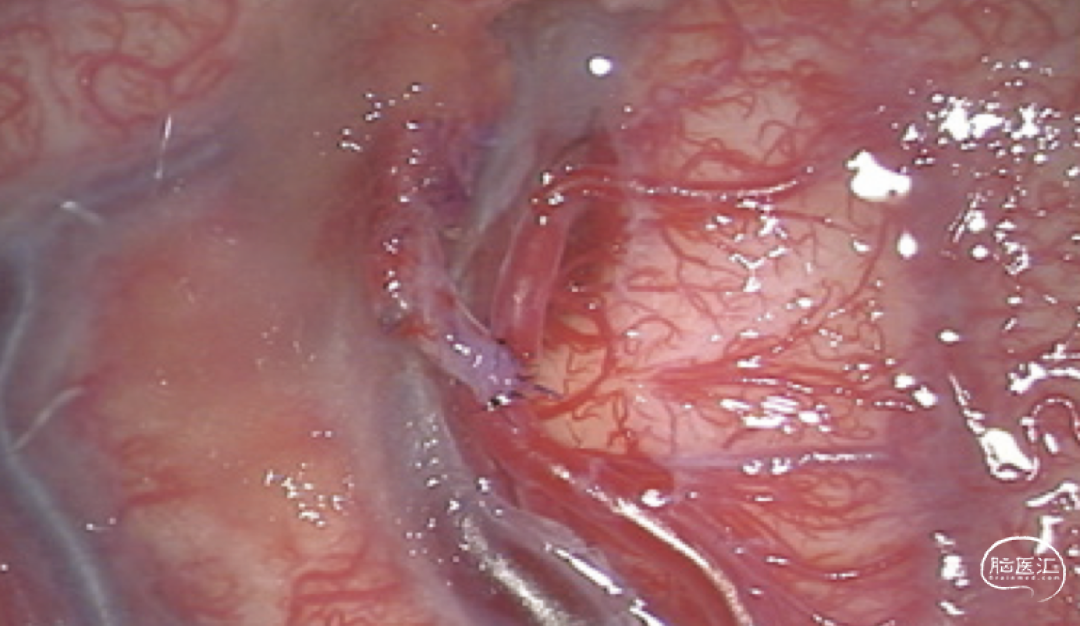

直接的颅内外动脉搭桥嘛,就是直接把颈外动脉的分支和缺血的脑半球里的皮质动脉连起来。间接的血运重建呢,就是拿颈外动脉分支供血的那些组织,转移到缺血的脑半球表面,让它和下面的皮质血管搞个侧支循环,好让缺血区恢复供血。